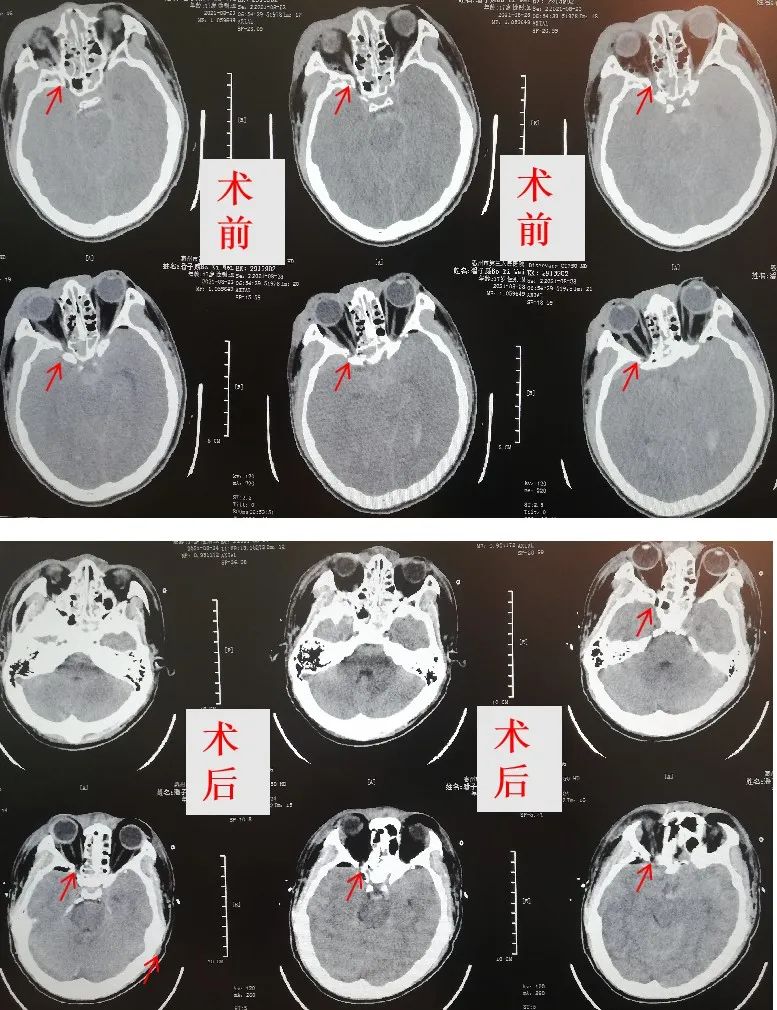

患者CT影像结果

手术前后对比

因该病例多部位颅脑损伤,手术复杂,风险极高。张红波主任、胡永珍住院总医师、刘惜弟主治医师,麻醉科梁豪主治医师及手术护理人员等经过6小时的奋战,顺利完成“右侧视神经损伤减压+脑脊液鼻漏修补”等手术。术后患者瞳孔较术前缩小,鼻腔流血及流液等情况消失!目前,患者意识恢复,遵嘱活动,仍在继续康复治疗!